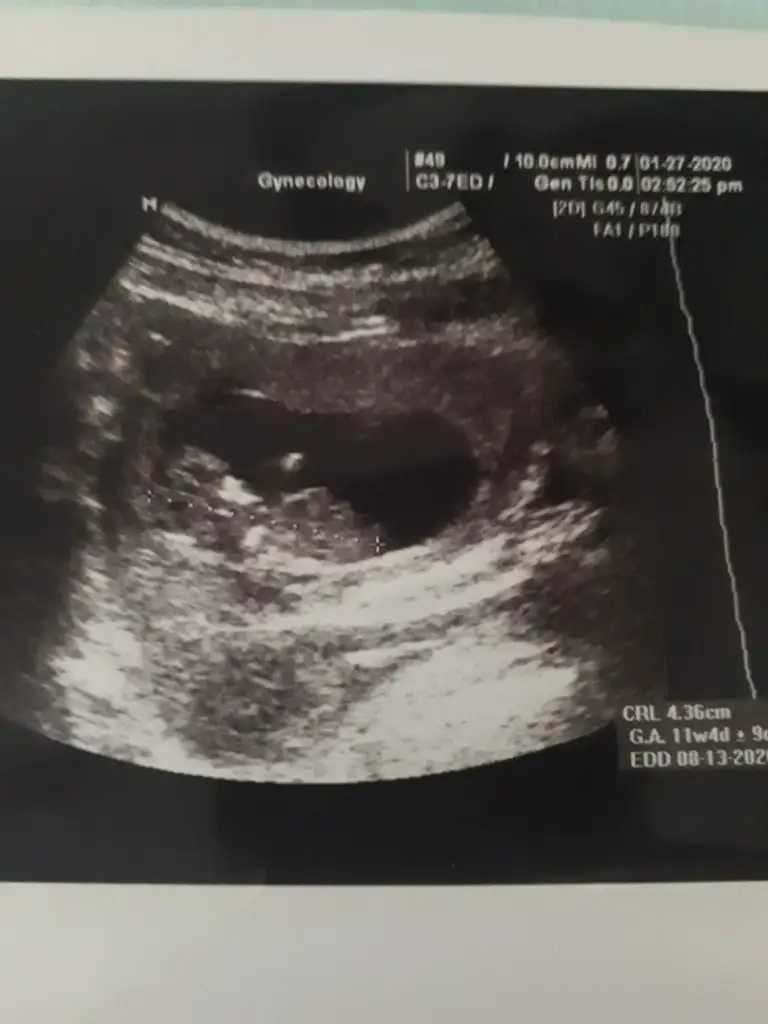

Kızçelet merhaba ☺️ Aşırı rica etsem de benim bebişimi de yorumlasanız olur mu doğum ağustosta inşAllah çin takvimi vs. Herşey de erkek çıktı içime de erkek doğuyor ama sağlıklı olsun tabi kız istiyoruz ☺️ Nub teorisine göre sanki kız gibi geldi bana bilen ilgilenen yorum yaparsa çok dua ederim ona 🥰🥰🥰

• A7191D7F-F9F6-4E86-BC5A-9F422ECC0F60.webp

A7191D7F-F9F6-4E86-BC5A-9F422ECC0F60.webp

21,9 KB · Görüntüleme: 57

Hayir kiz :) nipt test sonucu kiz cikti

Nubu karanlık kalmış ama kız nubu dediğim usg de vardı pozisyon gerçekten yanıltıyor 1 usgde ne dik nede paraleldi karşıya bakıyordu kafa şeklinide ekleyerek erkek olabilir dediğim usgde vardı hayırlısı olsun 3 kız annesi olmak ta ayrı bir guzel saglıkla gelsin prenses 😍🙇

Kızçelet merhaba ☺ Aşırı rica etsem de benim bebişimi de yorumlasanız olur mu doğum ağustosta inşAllah çin takvimi vs. Herşey de erkek çıktı içime de erkek doğuyor ama sağlıklı olsun tabi kız istiyoruz ☺ Nub teorisine göre sanki kız gibi geldi bana bilen ilgilenen yorum yaparsa çok dua ederim ona 🥰🥰🥰

Net degil usg erkek gibi gibi diye ekliyorum 12 + usgde paylaşırsınız netleştirelim yada varsa başka usg paylaşın